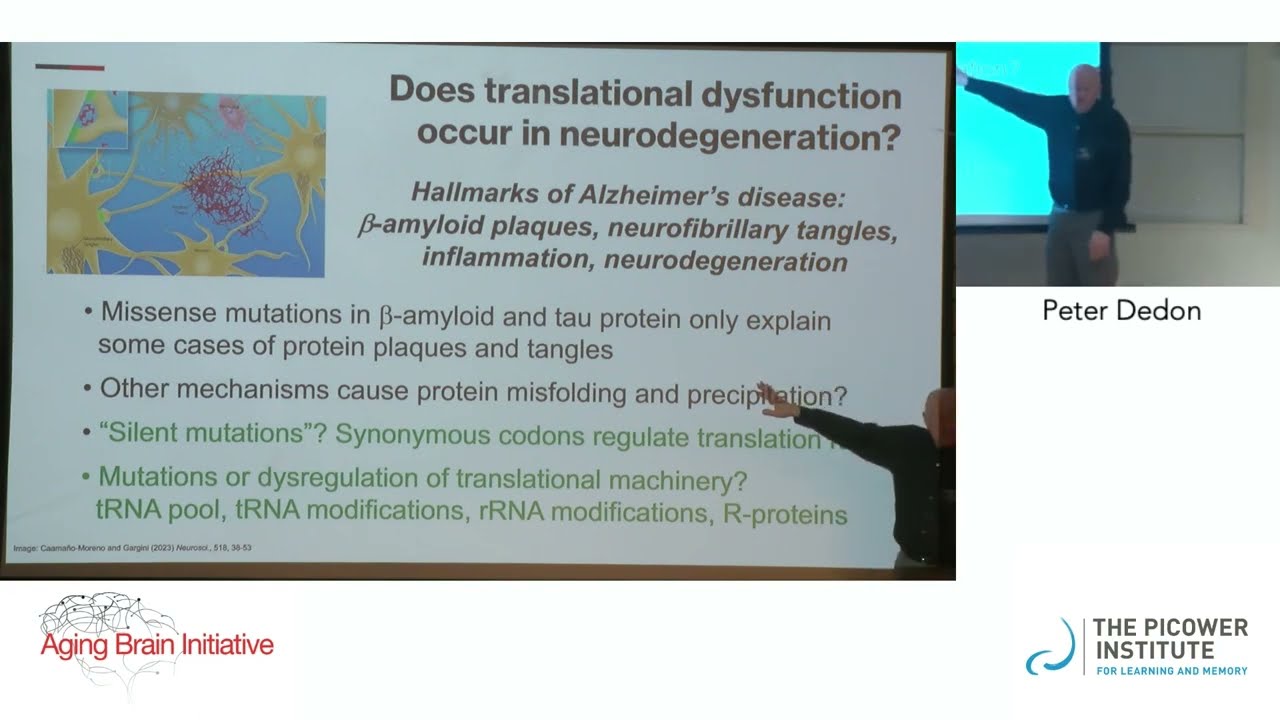

Biochemist Peter Dedon, the Singapore Professor in the Department of Biological Engineering, offered the hypothesis that the pathology of amyloid plaques and tau protein fibrillary tangles in neurodegenerative diseases involves dysregulation of translating messenger RNA into proteins in neurons. Based on their discoveries in cancer and infectious disease, his research team is investigating how aberrant modifications of transfer RNA (tRNA) and silent mutations of codons, which are critical players in regulating the protein translation process, can cause excessive protein synthesis and protein precipitation. Using a mouse model known to produce unhealthy forms of the tau protein, Dedon’s lab is investigating tRNA reprogramming and codon-biased translation of mRNAs in brain tissue, seeking to determine whether these might explain why tau pathology increases sharply as mouse models reach an age threshold.